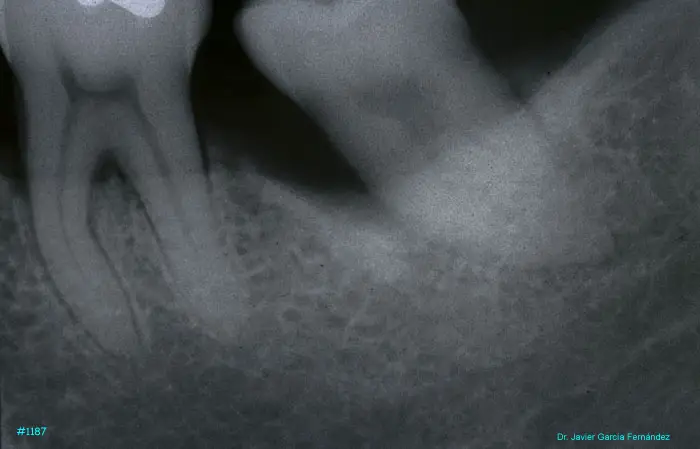

Atlas of Surgical Techniques in Periodontics. Chapter III. Atlas de Técnicas Quirúrgicas en Periodoncia